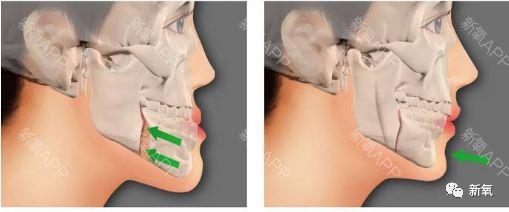

看下面的骨骼图,左侧是地包天,右侧是正常颌的。可以很明显的看见左侧下颌发育过度,上颌发育不足。

看下面这个真人案例,仅在整牙的矫正下,不仅下牙列回到正常的位置,连原本被限制发育、显得凹陷的中面部也变得正常,明显侧脸变得饱满了。

如果错过这个时期,骨骼全部定型后想要矫正这个问题,就只能动骨了···

而且仅将下颌骨推进去也无法让上颌再长出来,也就意味着:之后还需要将受到影响发育不足的鼻基底、鼻子补起来。(注意看右边的鼻基底和上颌依然是扁平的)